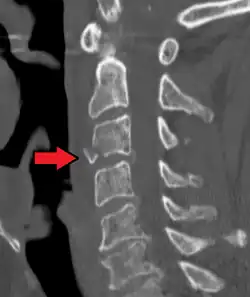

| A fracture of the base of the dens (a part of C2) as seen on CT | |

On CT scan or X-ray, a cervical fracture may be directly visualized. In addition, indirect signs of injury by the vertebral column are incongruities of the vertebral lines,[7] and/or increased thickness of the prevertebral space:[8]